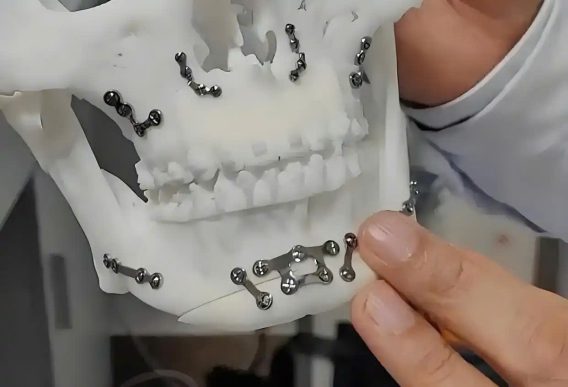

Gãy xương là một chấn thương phổ biến nhưng nghiêm trọng, thường đòi hỏi phải phẫu thuật cố định và hợp kim titan chính là “vũ khí bí mật” trong tay các bác sĩ chỉnh hình.

Được sử dụng để chế tạo tấm thép, ốc vít, khớp nối, và thậm chí cả xương nhân tạo, hợp kim titan hầu như không được cơ thể con người chấp nhận trong nhiều thập kỷ, điều này đã từng là vấn đề với các kim loại khác từ lâu, vậy tại sao hợp kim titan có thể xâm nhập vào cơ thể con người và cùng tồn tại một cách hòa bình? Khoa học đằng sau điều này sâu sắc hơn bạn nghĩ rất nhiều.

Hợp kim titan được sử dụng phổ biến nhất trong phẫu thuật gãy xương, ví dụ, gãy xương vụn cần phải dùng nẹp thép và vít để ghép các xương gãy lại với nhau, một ví dụ khác là hoại tử chỏm xương đùi ở người cao tuổi, cần thay khớp nhân tạo, trong đó hợp kim titan là vật liệu được ưu tiên, các dị tật bẩm sinh, vẹo cột sống và tái tạo sau khi cắt bỏ khối u xương cũng rất cần thiết.